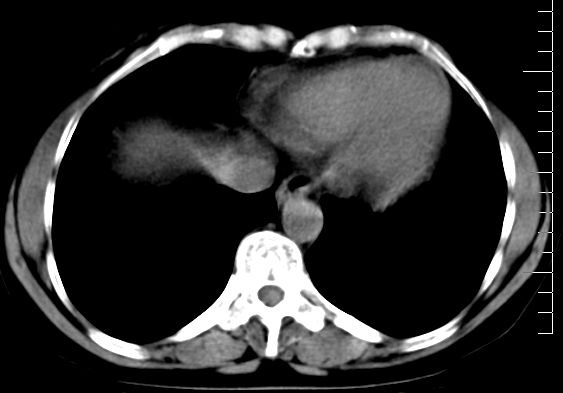

f、52岁,反复上腹部疼痛2年。肺结核病史10多年,胸片双上肺结核纤维化。

第一天做平扫,第二天做强化

ct表现:

肝大小形态未见异常,肝内外胆管无扩张,肝s8段见一动脉期明显血管样强化结节,门脉期呈高密度,延迟期呈等密度,胆囊不大,增强扫描见胆囊及胆囊颈管壁增厚,有强化。

双肾灌注良好,代谢增快,动脉期肾盂见造影剂,左肾下极背侧见一略低密度病灶,延迟期见似不强化囊肿,双侧肾上腺未见异常。

胰腺及脾未见异常。肾门水平腹膜后见小淋巴结。腹腔未见积液征象。